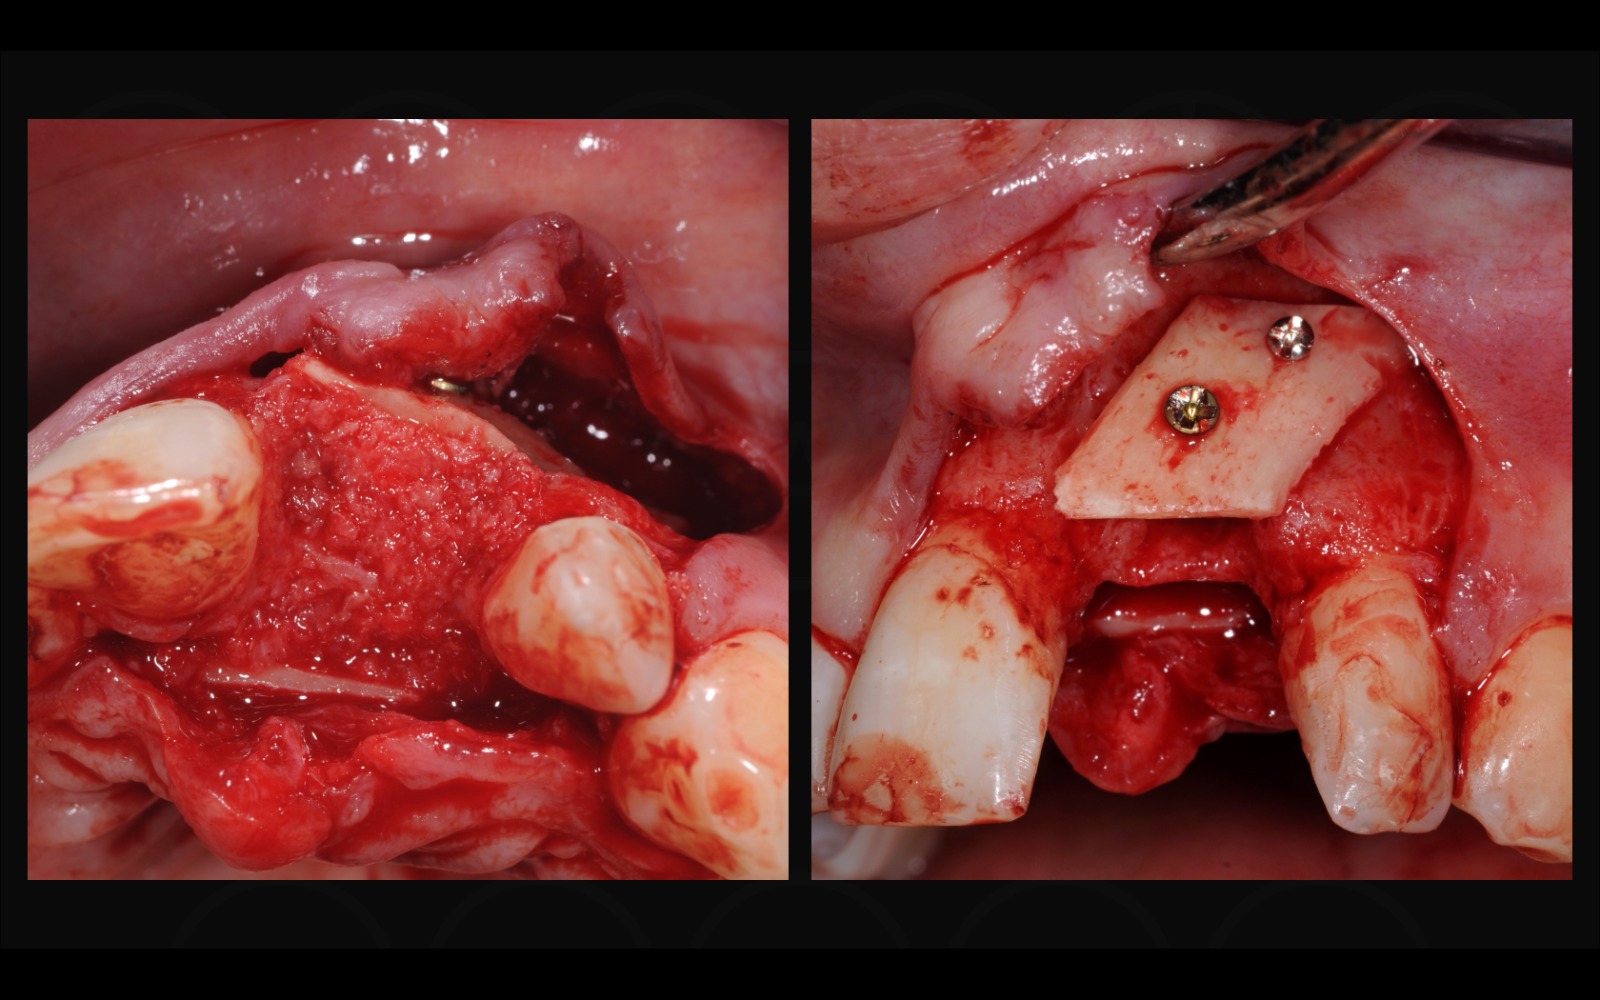

BBA (Biological Bone Augmentation) - augmentace kosti za použití pouze autologního materiálu. Praktický kurz techniky prof. Khouryho (SBB technika).

Praktickou náplní kurzu je pak především kompletní "step by step" seznámení se s technikou SBB (split bone block). Odběr kostního bločku, jeho zpracování a odběr autologních kostních pilin, 3D rekonstrukce kostních defektů za použití kostních plotének a autologní kosti.